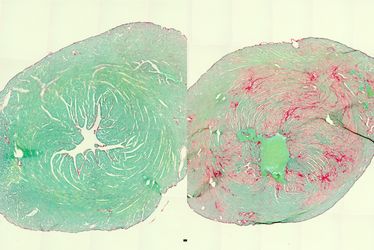

Herz einer gesunden (l.) und einer kranken Maus (Schnittbilder). Durch Bindegewebseinschlüsse (r., rot) ist das kranke Herz weniger leistungsfähig (Abb.: Kenichi Kimura/UKB)

„Die Mutation führt dazu, dass BAG3 zusammen mit Partner-Proteinen unlösliche Komplexe bildet, die immer größer werden“, sagt Hesse. Dadurch kommen die Reparaturprozesse zum Erliegen – die Muskulatur wird immer weniger leistungsfähig. Zudem entsteht mit der Zeit eine toxische Protein-Anreicherung, die schließlich zum Tod der Muskelzelle führt. „Die Folgen werden meist zuerst am Herz sichtbar“, so Hesse. „Dort wird Muskel sukzessive durch Narbengewebe ersetzt. Dadurch sinkt die Elastizität des Herzens, bis es kaum noch Blut pumpen kann.“

Bei den Betroffenen ist daher meist schon im Kindesalter eine Herztransplantation erforderlich. Dennoch hilft diese Maßnahme ebenfalls nur temporär, da die Krankheit auch die Skelett- und Atemmuskulatur erfasst. Oft sterben die Erkrankten daher schon in jungen Jahren.